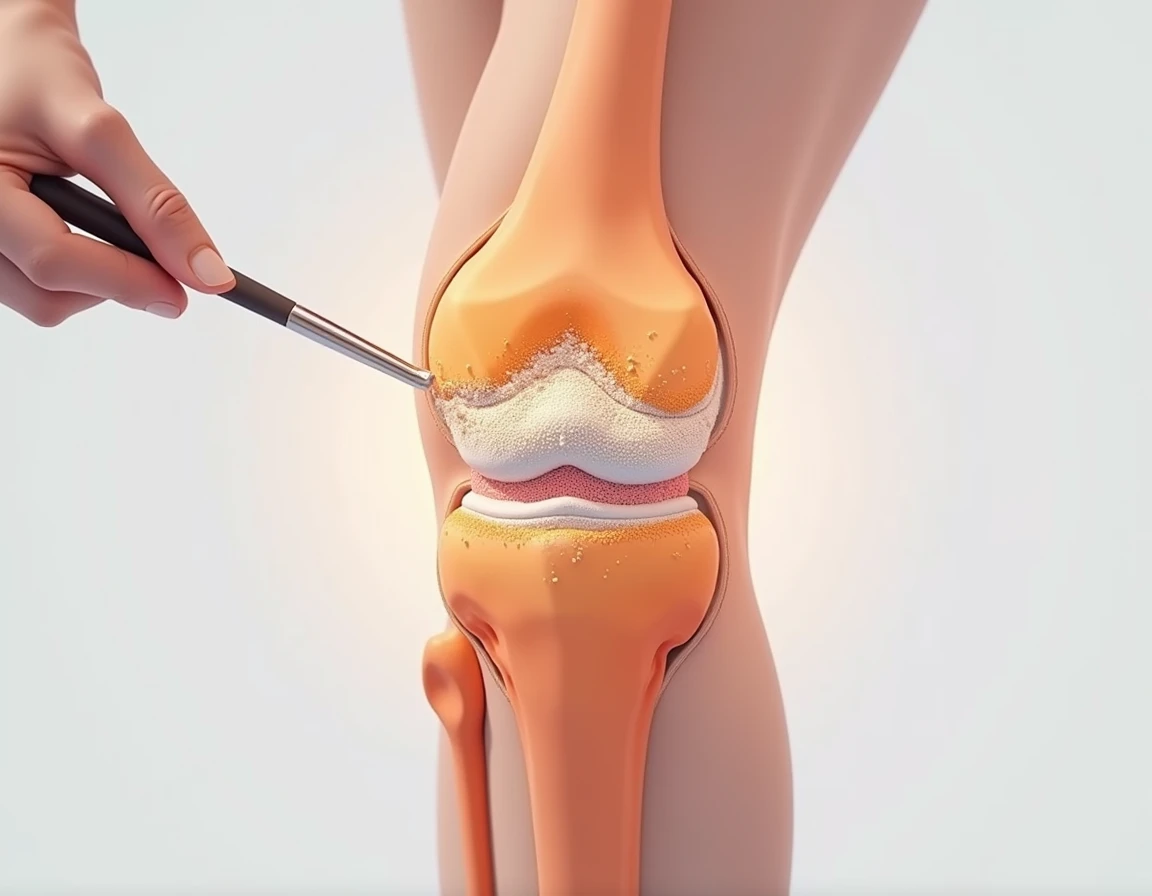

Close-up of human knee,There is a bone in the middle, knee, Knees, surreal bone structure, Protruding bones, Realphotos, orthographic view, Look across the shoulder, medical depiction, Osteoarticular joints, computer generated, hyper realisitc, sharp bone structure, joint, digital painted

Close-up of human knee

medical depiction

Osteoarticular joints

sharp bone structure